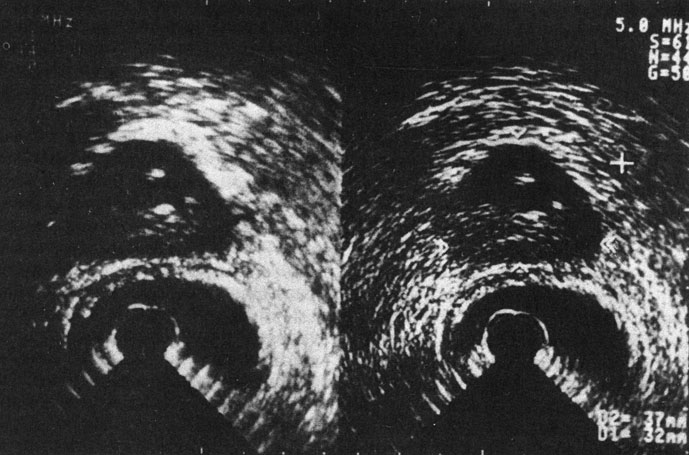

Патогенетические факторы простатитов можно разделить на 2 группы: обусловленные анатомическими и физиологическими особенностями предстательной железы и связанные с заболеваниями других органов и систем. Анатомически предстательная железа состоит из 30-50 ацинусов - тубулоальвеолярных железок. По своему расположению они образуют переднюю, заднюю и 2 боковые доли предстательной железы, но не имеют ничего общего с долями аденомы предстательной железы - гормональной доброкачественной опухоли, развивающейся из парауретральных желез. Каждая из железокацинусов заканчивается достаточно длинным, извитым выводным протоком, покрытым изнутри криптообразной слизистой оболочкой (рис. 20). Поступление секрета предстательной железы во время оргазма или эмоционально-сексуального возбуждения зависит от уровня тестостерона и других половых гормонов в крови, состояния вегетативной нервной системы, тонуса гладкой мускулатуры. Однако не всегда неполное поступление секрета предстательной железы зависит от этих причин. Анатомически предопределено медленное поступление секрета по выводным протокам в заднюю часть уретры, тем более это имеет место при уже начавшемся воспалении, когда просветы протоков забиты лейкоцитами, клетками слущенного эпителия, слизью, бактериями; иногда образуются гнойные пробки. Такова одна из анатомических особенностей предстательной железы, предрасполагающая к затяжному воспалению. Другой особенностью является слабость жомов выводных протоков ацинусов, открывающихся на задней стенке задней части уретры (рис. 21). При наличии уретрита при промывании просвета мочеиспускательного канала патогенные бактерии могут легко проникнуть в предстательную железу. Здесь же рядом расположены отверстия двух семявыбрасывающих протоков, довольно коротких, по которым инфекция и воспалительный процесс могут легко распространяться в семенные пузырьки. Разделение паренхимы предстательной железы на центральную (краниальную) и периферическую (каудальную) части, находящиеся соответственно под влиянием эстрогенов и андрогенов, обусловливает проникновение в боковые отделы железы инфекции из задней части уретры и семявыбрасывающих протоков. Центральная, или краниальная, зона подвержена лишь гематогенному заражению. Здесь из парауретральных железок растет аденома предстательной железы. Среди других особенностей, предрасполагающих к простатитам, следует назвать обильные анастомозы между венами таза и предстательной железы, в результате чего малейший венозный застой в тазу приводит к венозному стазу в ней, а это, как известно, не способствует быстрой ликвидации воспаления. Плотность фиброзной капсулы обусловливает увеличение внутрипредстательного давления при наличии инфильтративной фазы воспаления и при рубцовом процессе. В связи с тем, что артериолы проходят внутри железы в соединительнотканных прослойках между железками-ацинусами, доставка лекарственных форм с током крови при простатите затруднена.

Рис. 21. Задняя стенка предстательного отдела мочеиспускательного канала. 1 - маточка семенного бугорка; 2 - отверстия семявыбрасывающих протоков; 3 - отверстия выводных протоков предстательной железы